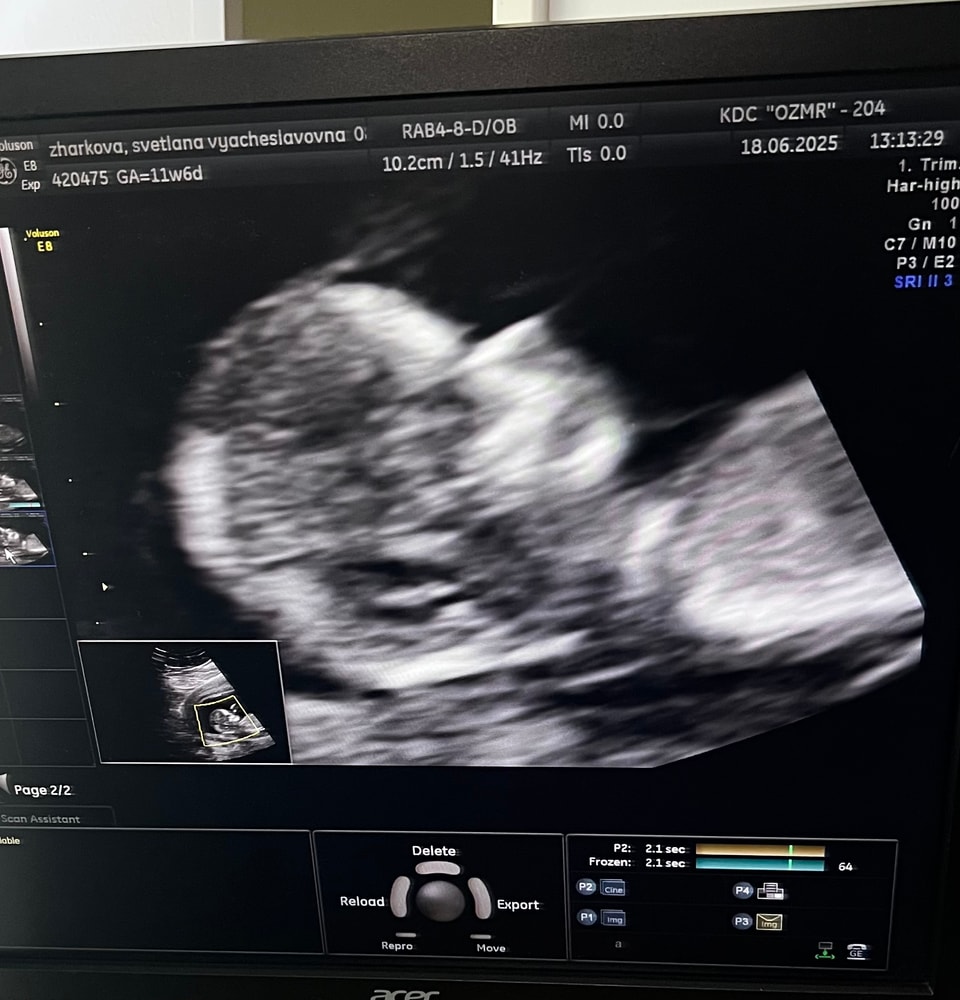

Скрининг 1 триместра

Наконец-то пройден😎

Как же быстро пролетело время, хотя переживала что будет тянуться)) движуха была постоянная, сдача анализов, приемы у врача, два раза успела полежать в стационаре с гематомой и она до сих пор со мной 😞 на больничном уже больше месяца в общей сложности, но это уже не важно. Главное что с малышом все хорошо, все риски минимальны, кроме преждевременных родов, надо наблюдать за шейкой, коротковата( 30.1 мм), немного опережаем срок.